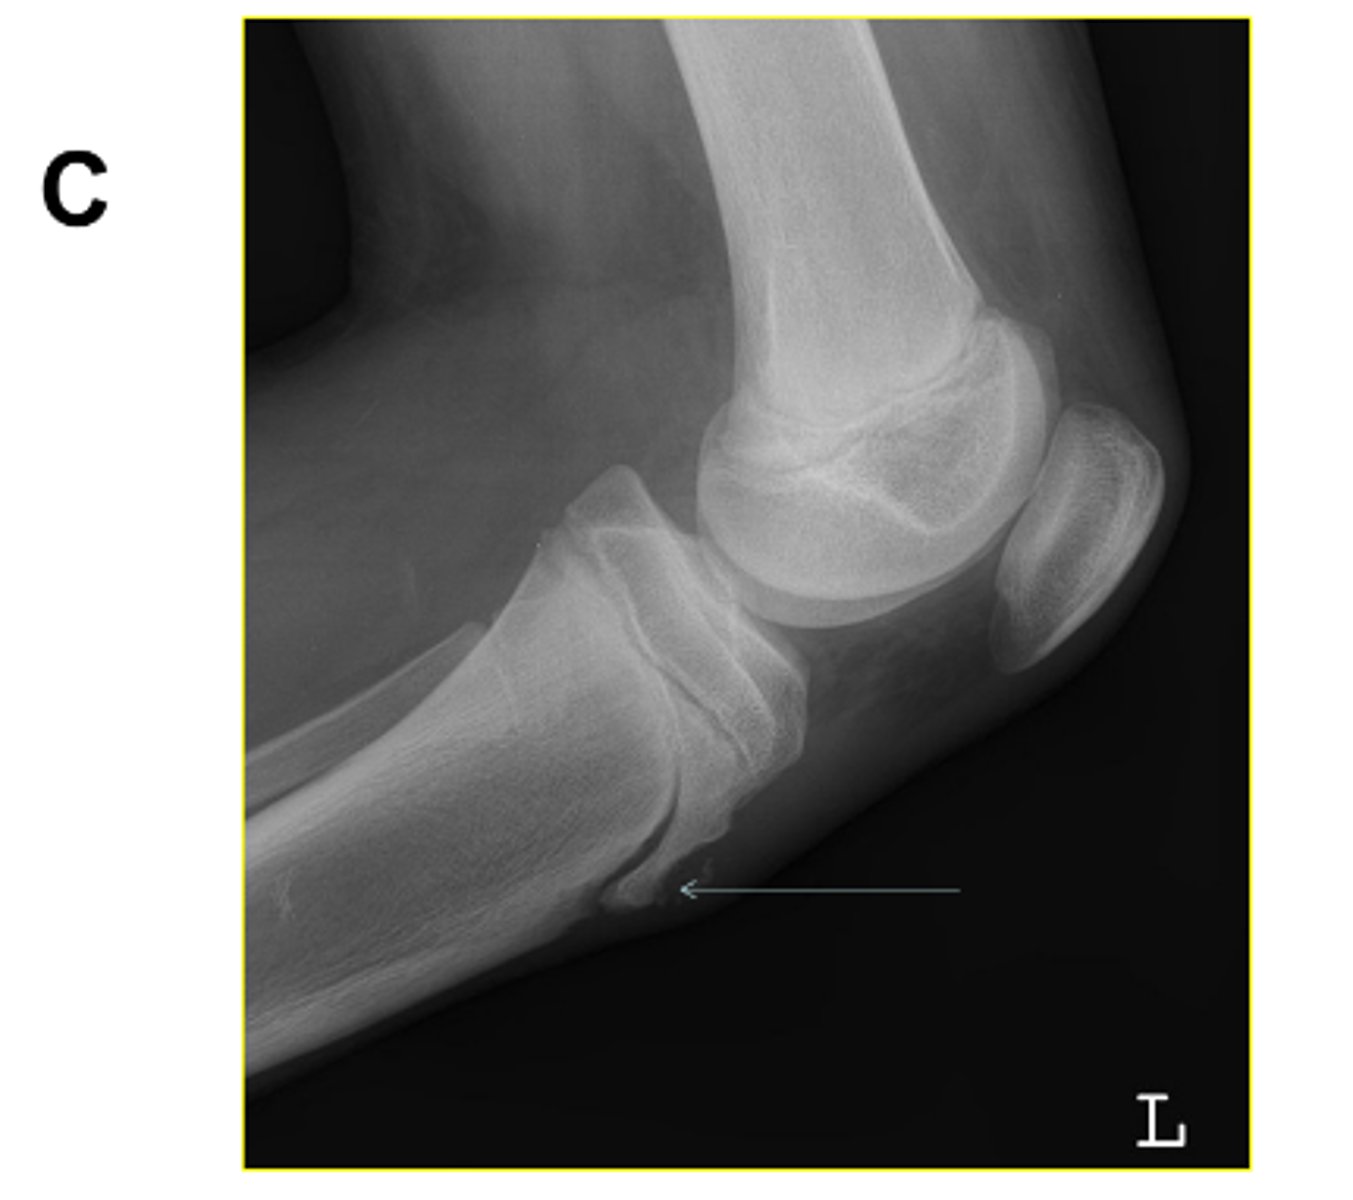

Identify the projection. (Be prepared to identify anatomy and critique for positioning on the quiz)

AP Oblique Knee, lateral rotation

What pathology is visualized on this image?

Osgood-Schlatter disease